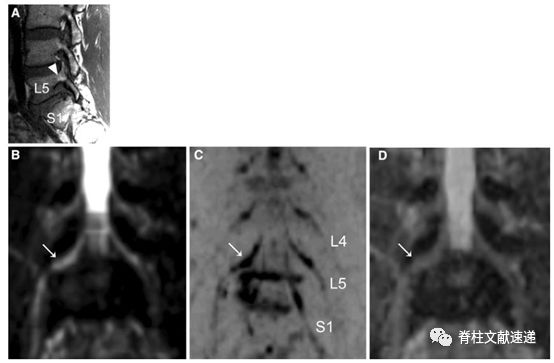

图注:66岁男性患者,L5-S1椎间孔狭窄,箭头显示L5椎间孔狭窄,神经周围脂肪信号消失。L4、L5和S1显示腰4、5和骶1神经根。D图是基于DWI冠状面计算的ADC图。箭头所示为被夹住的神经向上移位,并在孔内横移。